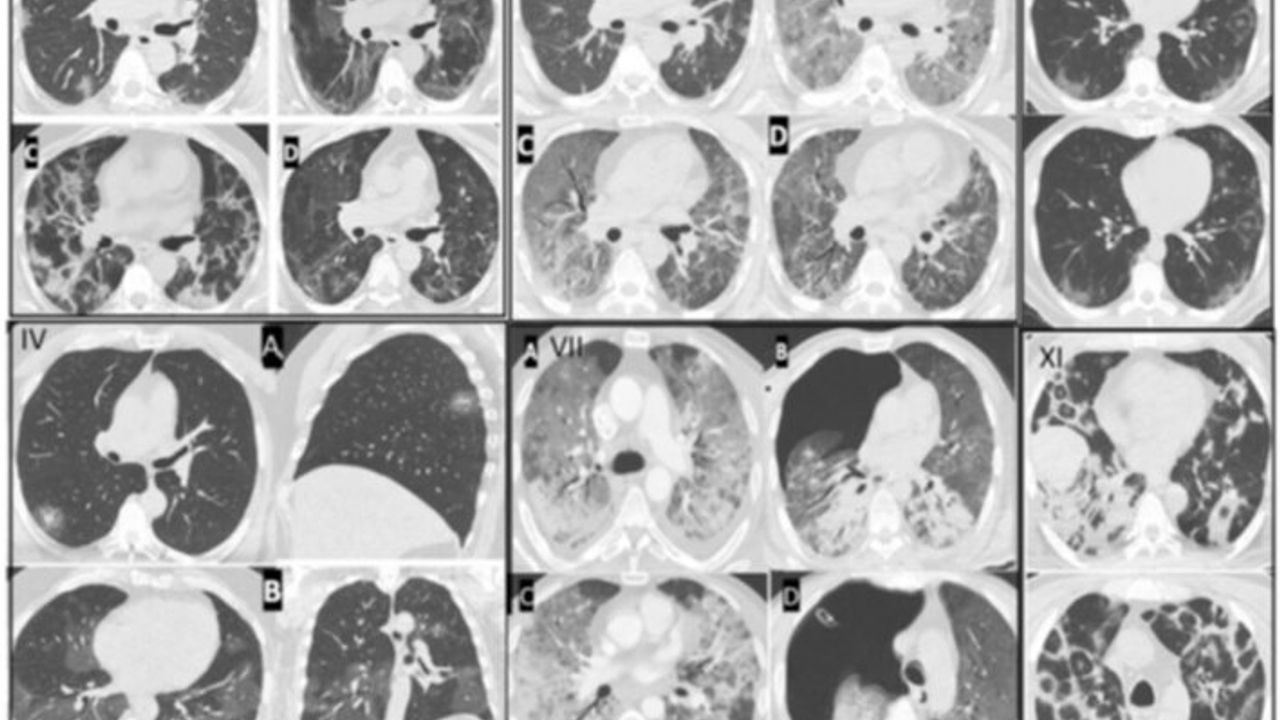

Prof. Dr. Şevket Özkaya: “Damar tıkanıklıkları, genç yaşlara indi.” Pandemi sonrası en çok akıllarda kalan soru bu virüsün toplumda kalıcı bir hasar bırakıp bırakmadığı konusu oldu. Altınbaş Üniversitesi Tıp Fakültesi Öğretim Üyesi, Göğüs Hastalıkları Anabilim Dalı Başkanı Prof. Dr. Şevket Özkaya, “Ülkemizde ve Dünyada "vasküler trombozlar" denilen damar tıkanıklığına bağlı hastalıkların özellikle genç yaşlarda görülmeye başlandığına dikkat çekti.Özellikle pandemi ile damar hasarı ve tıkanıklıkların genç yaşlara inmesinin COVID salgını mı yoksa aşıların mı neden olduğu sorusunun hem tıp camiasında hemde toplumda tartışmaları devam ettiğini söyledi. Prof. Dr. Şevket Özkaya, Altınbaş Üniversitesi Tıp Fakültesi Göğüs Hastalıkları Anabilim Dalı öğretim üyelerinin dahil olduğu 12.000’e yakın COVID 19 hastasının incelendiği önemli klinik çalışma yapıldığını belirtti.Bu araştırmanın sonuçlarına göre COVID 19 virüsü ile enfekte kişilerde ve özellikle akciğer tutulumu olanlardaendotel hasarının görüldüğünün saptandığına işaret etti. Prof. Dr. Şevket Özkayabilimsel araştırmalara göre bir insanda damar tıkanıklığı olması için 3 faktörün etkili olduğunu anlattı. “En önemli faktör,endotel hasar dediğimiz damarlarımızın en içteki katmanında hasar oluşması. İki,hiperkoagulabilire dediğimiz aileden gelen kalıtsal ve sonradan gelişen pıhtılaşmaya yatkınlık. Ve son olarak da Tıpta "staz" dediğimiz ve halk diliyle hareketsiz kalmak olarak tabir edilen faktörler etkili” bilgilerini paylaştı. “Virus hala aramızda ve yeniden ağır ve kritik hastalar görmeye başladık” Prof. Dr. Şevket Özkayabuna göre, uzun süren hareketsizlik yani 2-3 saatten fazla oturarak hareketsiz yapılan yolculuklar, hastalıkların neden olduğu uzun süre yatakta olmak gibi kan akışının yavaşladığı durumlarda, ailesinde damar tıkanıklığı öyküsü olanlarda artık damar tıkanıklıklarının genç yaşlara indiğini vurguladı. Bunun birincil sebebinin COVID 19 virüsünün vücutta yerleştiğinde kanı oluşturan plazmayı,tahrip edici hale getirerek endotel denilen damarların en içteki katmanını tahrip ederek damar tıkanıklığının ilk basamağını ortaya çıkardığını anlattı. Bunun tetikleyici faktör olduğunun altını çizen Özkaya, “Aşılar bu hastalıkta bizi koruyan bir faktör idi. Genç yaşlarda damar tıkanıklıklarının görülmesi, aşılardan bağımsız ve öncelikle COVID 19 virüsünün etkileri ve bireysel faktörlere bağlıdır.Şunu unutmamak lazım; salgın bitti ama virus hala aramızda ve yeniden ağır ve kritik hastalar görmeye başladık.” diyerek uyarılarda bulundu. ARAŞTIRMA BULGUSUNDAKİ FOTOGRAF DETAYLARI: * III resimde COVID 19 ile enfekte olan bir hastada damardaki hasar gözleniyor. * IV resimde COVID 19 virüsünün akciğerde ilk başlangıcını ve XI ve diğer resimlerde akciğerlerdeki ilerlemiş hasar görülüyor. * IX resimde COVID 19 virüsünün beyindeki tutulumu ve XII resimde COVID 19 ciltte COVID 19 tutulumunu görüyoruz. Hem damar tutulumun patolojik görünümü hem de organ tutulumunun görüntüleri birbiri ile aynı olduğunu görüyoruz. * Dünyada daha önce böyle bir tespit olmadığını ifade eden Prof. Dr. Özkaya, "Hem mikroskobik damar tutulumu hem de cilt beyin akciğer gibi organ tutulumlarının görüntüleri aynı" değerlendirmesini yaptı.  (HABER MERKEZİ)